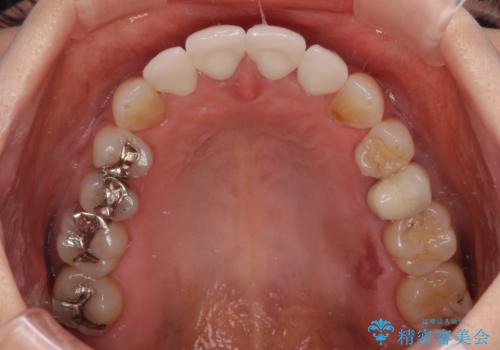

前医で仮歯を装着する前の口元の写真をいただき、咬み合わせや形態を参考にしながら仮歯で仕上がりをイメージし、最終的に満足のいくオールセラミッククラウンを装着することができました。